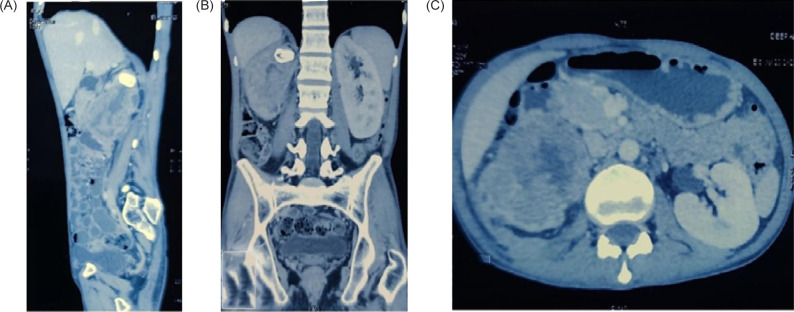

Germ cell tumor (GCT) is a neoplasm typically found in childhood, commonly originating from the testis or ovary. While there have been reported cases of GCT occurring in various extragonadal sites, primary intrarenal GCT is exceptionally rare. We present a case of 37-year-old male who presented with right upper abdomen pain. Imaging revealed a sizable mass within the right kidney. The patient underwent surgical resection of the renal mass during which there was perirenal infiltration into the duodenum and dense desmoplastic reaction all around. Subsequent histopathology confirmed the diagnosis of primary intrarenal nonseminomatous germ cell tumor (NSGCT). The patient underwent four cycles of adjuvant bleomycin, etoposide, and cisplatin (BEP) chemotherapy; at 6 months of follow-up, he is fine. The objective of this case report is to underscore the importance of considering NSGCT as a potential rare differential diagnosis in cases of renal neoplasms and further plan for the management.

Abstract Image